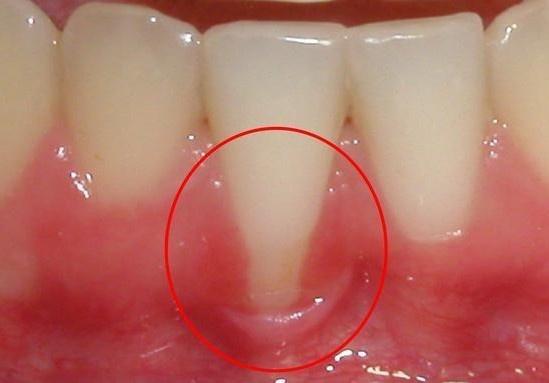

什么是牙齦萎縮呢?

牙齦萎縮通常是由牙周組織疾病所引起的,通常的表現(xiàn)的是牙齦緣向牙根方向退縮,后使牙根暴露,所以會使我們的牙齒看起來越來越長。

牙齦一旦形成萎縮,其結(jié)果是不可逆的。失去牙齦包裹的牙齒不僅會伸長、牙縫變大影響口內(nèi)美觀;還會使牙根暴露,當(dāng)失去牙齦的保護(hù)時,牙根會很容易受到刺激敏感,遇到冷熱酸甜等刺激性食物容易不適。而且隨著牙縫變大,食物殘渣容易塞嵌,這也加大了患根面齲的風(fēng)險。